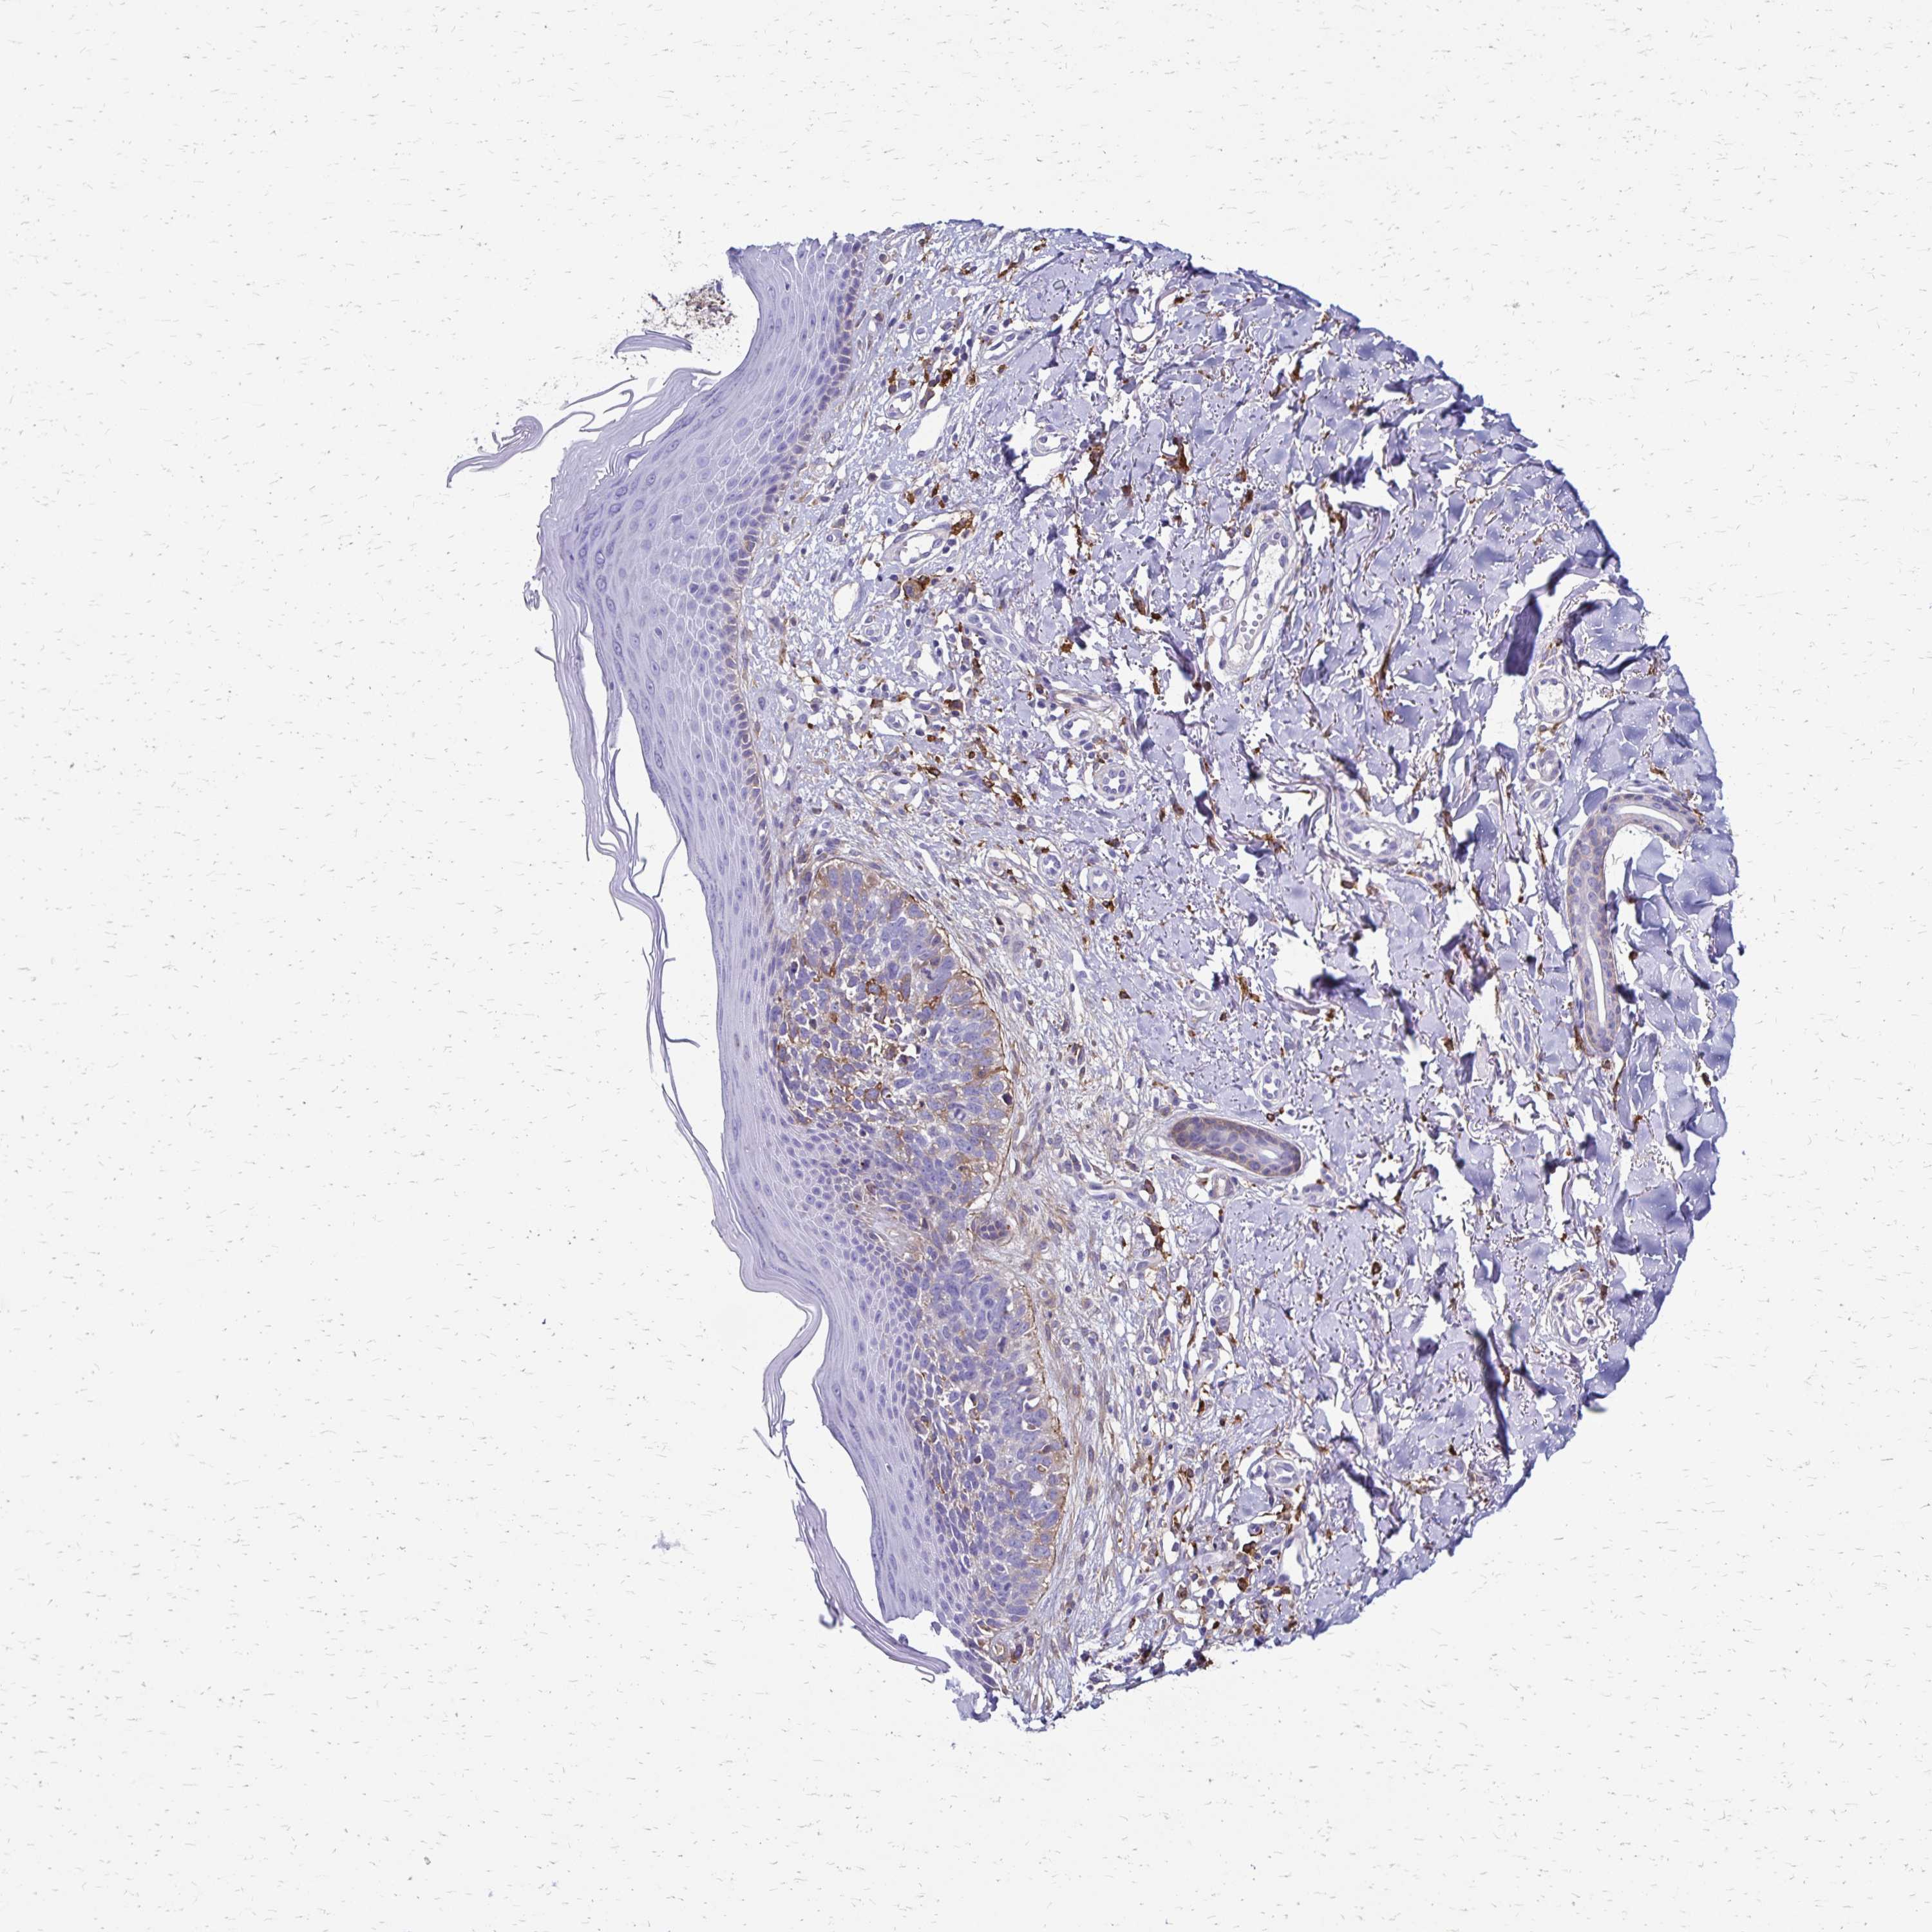

Basal cell and squamous cell cancer

SKIN CANCER - Protein expressioni

A mouse-over function shows sample information and annotation data. Click on an image to view it in a full screen mode. Samples can be filtered based on level of antibody staining by selecting one or several of the following categories: high, medium, low and not detected. The assay and annotation is described here.

Antibody stainingi

Antibody staining in the annotated cell types in the current human tissue is reported as not detected, low, medium, or high, based on conventional immunohistochemistry profiling in selected tissues. This score is based on the combination of the staining intensity and fraction of stained cells.

Each image is clickable and will lead to virtual microscopy that enables deeper exploration of all samples and also displays staining intensity scores, fraction scores and subcellular localization as well as patient and tissue information for each sample.

Antibody HPA055338

Antibody HPA056015

Staining

High

Medium

Low

Not detected

Intensity

Strong

Moderate

Weak

Negative

Quantity

>75%

75%-25%

<25%

None

Location

Nuclear

Cytoplasmic/membranous

Cytoplasmic/membranous,nuclear

Basal cell carcinoma

Squamous cell carcinoma, NOS